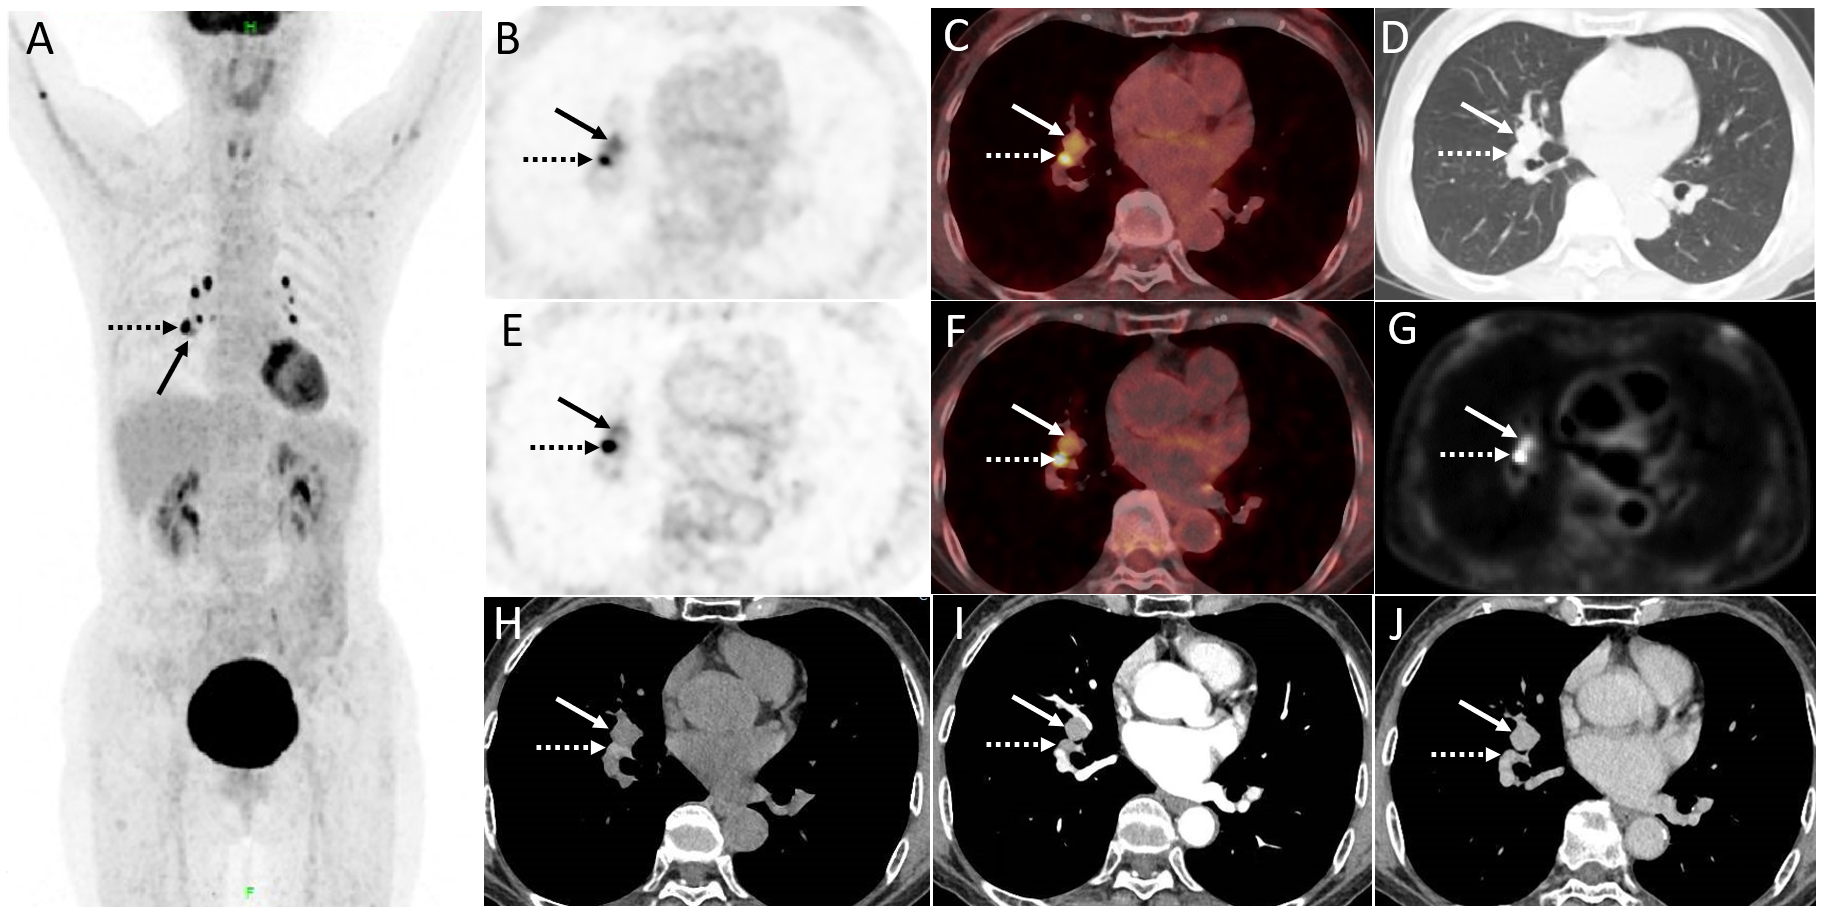

A 70-year-old woman underwent distal gastrectomy due to gastric adenocarcinoma in 2015. The patient had no complaints of specific discomfort during follow-up, and regular gastroscopy showed no evidence of local recurrence for 6 years after surgery. The blood serum levels of CEA, SCC, NSE, CA125, CYFRA21-1, and ProGRP were normal. Follow-up CT revealed a suspicious mass in the right hilar of the lung mimicking mediastinal lymph nodes. The images of contrast-enhanced CT and dPET/CT are shown in Figure 1. The contrast-enhanced CT revealed a markedly enhanced endobronchial mass (1.6 cm × 1.5 cm) adapting to the right intermediate bronchus. Further dPET/CT demonstrated the described right hilar mass with a moderately increased FDG uptake (SUVmax 3.9 and 3.8 for regular and delay scans, respectively) and a relatively high Ki value (0.029 mL/g/min). The symmetrical mediastinal lymph nodes had intense FDG uptake (SUVmax 12.3 and 17.4) but a relatively low Ki value (average Ki of 0.021 mL/g/min).

(A) The maximum intensity projection image (MIP) of PET/CT. The described right hilar mass (1.6 cm × 1.5 cm) displayed in (B, C) regular scan, (D) lung window, and (E, F) delay scan (arrow, SUVmax of 3.9 and 3.8, respectively) mimicking mediastinal lymph nodes with intense FDG uptake (dotted arrow, SUVmax 12.3 and 17.4. respectively). (G) Quantification analysis of dynamic parameters (Ki, net influx rate) shows that the mediastinal lymph nodes had a significantly high uptake of FDG but a relatively low Ki value (average Ki of 0.021 mL/g/min), while the Ki value for endobronchial mass (arrow) was 0.029 mL/g/min. (H–J) Contrast-enhanced CT revealed a markedly enhanced endobronchial mass adapting to the right intermediate bronchus.